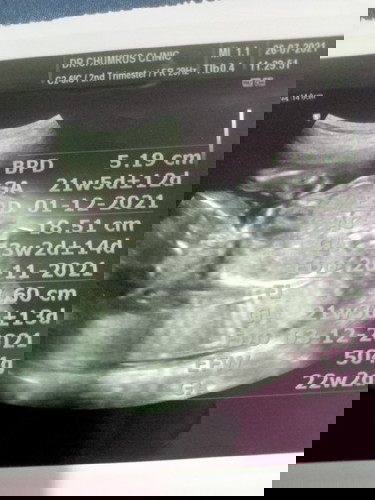

คุณหมอไม่เห็นบอกอะไรเลยบอกแค่ว่าลูกหนัก5ขีดท้อง22w

เห็นคุณหมอวัดขนาดไม่รู้ว่าวัดขนาดส่วนไหนของลูกบ้างนะในใบซาวด์แม่คนไหนมีใบซาวด์บอกแบบนี้บ้างนา,,?

บ้านนี้ ช่วง 20 w หมอที่ฝากนัดซาวอย่างละเอียดเลยค่ะ ดูความสมบูรณ์ทุกส่วนอวัยวะของน้อง จะบอกหัวใหญ่ปกติไหม หัวใจเบือดเข้าออก นิ้วต่างๆ ปากแหว่งไหม ตัวปกติไหม รูปภาพจะมีแต่อวัยวะที่หมอเช็คค่ะ